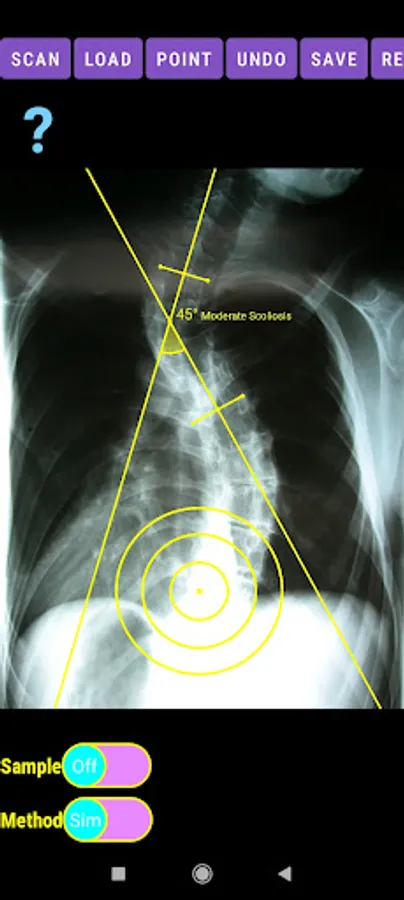

-Offers a very convenient way to determine the most accurate possibly way at once. By marking four points at the same X-ray, at each spine the App calculates the Cobb angle. In cases where values are out of normal ranges, the scoliosis is categorized according to measured angle as mild, moderate, severe. To simplify the process and to minimize inter-observer errors usually by not selecting the actual end vertebra, the app offers also in ext mode the ability to draw the vertical reference line through the patient’s sacrum and to identify more easily the end vertebrae (ext method).

-The app also is independent from errors produced by image inclination. Especially developed module allows the user to measure accurately without to worry about the tilting of the picture or the X-ray.

The app offers a very convenient way to asses spinal deformity by measuring the Cobb angle. The first thing is to load one image from your photo library or capture a photo from x-rays photos of a patient. The app offers two measuring methods, the simple (Sim.) and the extended (Ext.). By clicking the relevant option, the option is highlighted and the respective method is activated.